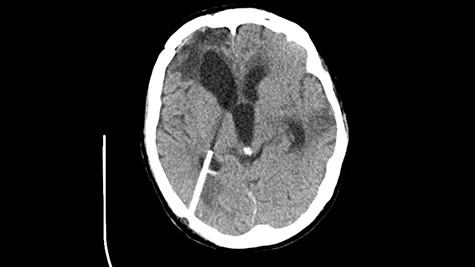

Head CT after polypectomy—seen defects of the upper left orbital wall. (Department of Neurosurgery own material).

In described case, a head CT scan after polypectomy confirmed the subarachnoid hemorrhage (Fig. 1). In addition, the presence of air in the ventricular system was visible, and presence of defects of the upper left orbital wall and ethmoid on both sides (Fig. 3). In the CT scan sphenoid sinus, frontal and ethmoidal sinuses on both sides and right maxillary sinus airless, filled with blood and soft tissue. The changes also concerned the lateral part of the left maxillary sinus (Fig. 4).

The present bone defects were most probably caused by the development of osteomalytic foci as a consequence of the spread of the inflammatory process within the diploe of flat skeletal skull bones, in the course of chronic rhinosinusitis. Both underestimating the severity of complaints in the course of chronic rhinosinusitis and delaying the implementation of surgical treatment led to massive bone destruction, which had an impact on the development of further complications after polypectomy (including subarachnoid hemorrhage). Performed angio-CT excluded any malformations and the probable cause of subarachnoid hemorrhage due to rupture of the aneurysm. Considering the radiological picture and the condition of the patient, it can be concluded that the persistent inflammatory process within sinuses led to dehsomination and subsequent bleeding into the subarachnoid space through discontinuity in the bone structure of the sinuses and orbits.